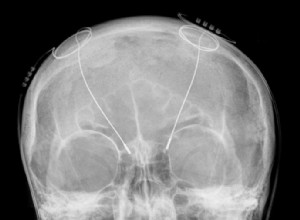

Stimulation cérébrale profonde : une déconnexion ciblée des zones motrices chez les patients parkinsoniens